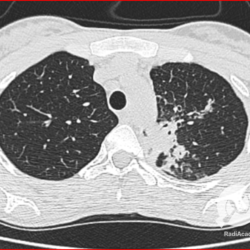

Os agentes etiológicos infecciosos são variados (bactérias, vírus, fungos, parasitas…), mas o que ocorre nos pulmões durante uma infecção por qualquer tipo de agente é a substituição do ar alveolar por secreção (pus, muco, eventualmente sangue ou necrose…) e com isso a manifestação radiográfica vai ser a mesma já que todas estas secreções apresentam a mesma densidade radiográfica: partes moles.

E o nome dado a esta alteração radiográfica que corresponde à substituição do ar alveolar por líquido é a consolidação alveolar.

Uma consolidação alveolar é, por definição, uma opacidade (imagem densa, branquinha) homogênea ou às vezes heterogênea (pela presença de calcificações ou cavidades), de limites mal definidos, exceto quando toca a pleura da parede ou das cissuras pulmonares. É um termo usado tanto em radiografia, como em tomografia computadorizada. Na tomografia, um outro termo é usado: vidro fosco, que é uma opacidade (branquinha mas não tanto como a consolidação), que borra o pulmão mas deixa ver os vasos de permeio (igual bigode de adolescente: dá pra ver todo o fundo).

Nós vamos mostrar aqui um pequeno apanhado de pneumonias de variados agentes, em diversos segmentos e lobos pulmonares, com extensões variadas. O objetivo é identificar o padrão radiológico de consolidação alveolar e não determinar o agente infeccioso, isso vai ser assunto para mais adiante. Aliás já antecipo que é fundamental saber localizar a lesão, porque alguns destes bichos gostam de determinados segmentos, alguns tumores também têm as suas preferências, então localização é fundamental. Se localização não fosse importante, um apartamento na beira do mar sairia o mesmo preço de um apartamento de frente pra BR-101, concordam?